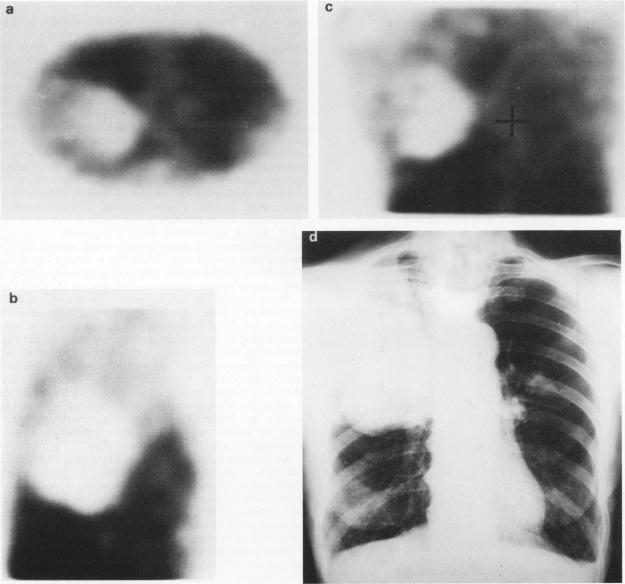

In order to assess the blood flow patterns through human lung tumours, 20 patients received 400-750 MBq 99TcmHMPAO intravenously 10 min before single photon emission computed tomography (SPECT). Ratios of uptake in the whole tumour relative to normal lung ranged from 0.35 to 1.53 (mean 1.01) with eight tumours showing less uptake than normal lung and ten showing greater uptake. In one patient the tumour was not distinguishable from surrounding lung and in another a large pleural effusion prevented evaluation. Tumour: lung ratios for central tumour regions ranged from 0 to 1.83 (mean 0.80) with 13 showing lower uptake than normal lung and five showing greater uptake. Duplicate scans were performed in eight patients demonstrating satisfactory reproducibility. This technique provides a simple and reproducible method for the assessment of tumour blood flow.

为了评估通过人类肺部肿瘤的血流模式,20名患者在单光子发射计算机断层扫描(SPECT)前10分钟静脉注射400 - 750 MBq的99TcmHMPAO。整个肿瘤与正常肺组织的摄取比值范围为0.35至1.53(平均1.01),其中8个肿瘤的摄取低于正常肺组织,10个肿瘤的摄取高于正常肺组织。在1名患者中,肿瘤与周围肺组织无法区分,在另1名患者中,大量胸腔积液妨碍了评估。中央肿瘤区域的肿瘤:肺比值范围为0至1.83(平均0.80),其中13个区域的摄取低于正常肺组织,5个区域的摄取高于正常肺组织。8名患者进行了重复扫描,显示出令人满意的可重复性。该技术为评估肿瘤血流提供了一种简单且可重复的方法。